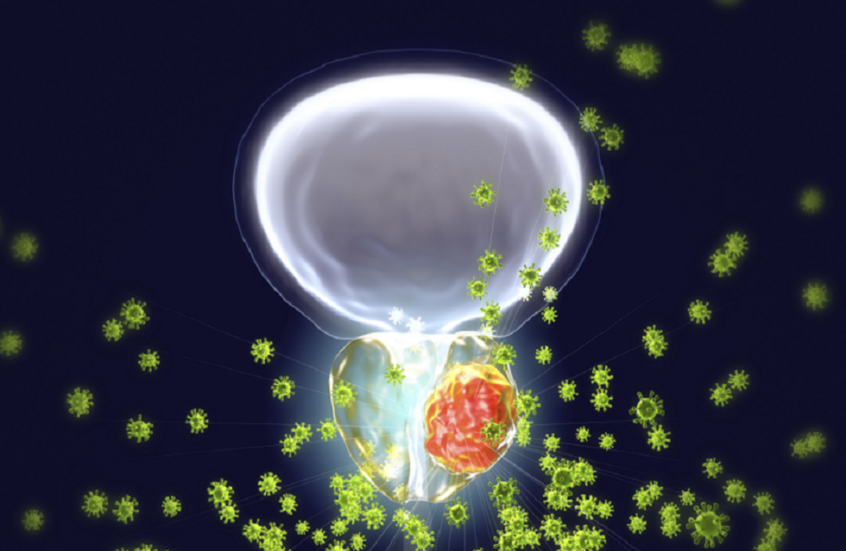

خطر خفي يومي يهدد الرجال بالإصابة بسرطان البروستات

حذر علماء من أن التعرض اليومي للبلاستيك، من عبوات الطعام ومستحضرات التجميل إلى الأدوات المنزلية، قد يشكل خطرا خفيا على صحة الرجال.

وأظهرت دراسة جديدة أن شظايا البلاستيك الدقيقة تتراكم داخل البروستات، حيث وُجدت مستويات أعلى بكثير في الأنسجة السرطانية مقارنة بالأنسجة السليمة من الغدة. وبينما أكد العلماء أن النتائج لا تثبت علاقة سببية بعد، فإنها تضيف إلى المخاوف بشأن التأثير الطويل الأمد للتعرض للبلاستيك على الجسم، خاصة مع ارتفاع حالات تشخيص سرطان البروستات في السنوات الأخيرة.

وحللت الدراسة، التي أجراها علماء في مركز لانغون الصحي بجامعة نيويورك، أنسجة البروستات المأخوذة من عشرة رجال خضعوا لاستئصال الغدة بالكامل كجزء من علاجهم من السرطان.

ووجد فريق البحث البلاستيك الدقيق في أورام تسعة من كل عشرة مرضى، مع وجوده أيضا في الأنسجة السليمة المجاورة لكن بكميات أقل. وفي المتوسط، احتوت الأنسجة السرطانية على نحو 40 ميكروغراما من البلاستيك لكل غرام من الأنسجة، مقارنة بـ 16 ميكروغراما في الأنسجة السليمة، أي ما يقارب ضعفين ونصف.

وأوضح العلماء أن هذه النتائج تفتح الباب أمام تساؤلات حول ما إذا كان التعرض الطويل الأمد للبلاستيك قد يزيد من خطر الإصابة بالسرطان، لا سيما في الأعضاء المعرضة للالتهابات المزمنة.

واستخدم العلماء في الدراسة معدات متخصصة لفحص عينات الأنسجة بصريا قبل تحليل كمية وتركيب البلاستيك الكيميائي، مع التركيز على 12 نوعا من البوليمرات الأكثر شيوعا في المنتجات الاستهلاكية. ولتجنب تلوث العينات، استُبدلت الأدوات البلاستيكية بمعدات من الألومنيوم والقطن ومواد أخرى غير بلاستيكية، وتم التعامل مع العينات في غرف نظيفة مصممة خصيصا لتحليل الجسيمات الدقيقة.

وقالت الدكتورة ستايسي لوب، المعدة الرئيسية للدراسة: "تقدم دراستنا أدلة مهمة على أن التعرض للجسيمات البلاستيكية الدقيقة قد يكون عامل خطر للإصابة بسرطان البروستات"، وأضافت أن الأدلة السابقة لم تكن كافية لإثبات علاقة مباشرة بين هذه الجسيمات والمرض.

وأوضح المعد الرئيسي، فيتوريو ألبرغامو، أن نتائج الدراسة "تسلط الضوء على الحاجة إلى تدابير تنظيمية أكثر صرامة للحد من تعرض الناس للبلاستيك"، مضيفا أن الفريق يخطط لدراسة كيفية مساهمة هذه الجسيمات في تطور السرطان، بما في ذلك احتمال تحفيزها استجابة مناعية مفرطة تؤدي إلى تلف الخلايا وتغيرات جينية سرطانية.

وأكد العلماء أن الدراسة قائمة على الملاحظة وبحجم صغير، ما يعني أنها لا تثبت أن الجسيمات البلاستيكية الدقيقة تسبب سرطان البروستات، وأن دراسات أكبر تشمل عددا أكبر من المرضى ستكون ضرورية لتأكيد النتائج.

وتتشكل الجسيمات البلاستيكية الدقيقة عندما تتحلل المواد البلاستيكية الأكبر حجما بفعل الحرارة أو الاحتكاك أو أشعة الشمس أو المعالجة الكيميائية، وتأتي من مصادر عديدة تشمل عبوات الطعام وزجاجات مستحضرات التجميل وألياف الملابس الاصطناعية والمنتجات المنزلية. ويمكن أن يبتلع الإنسان هذه الجسيمات عبر الطعام ومياه الشرب، أو يستنشقها من الهواء، أو يمتصها عبر الجلد. وقد وجدت دراسات سابقة الجسيمات البلاستيكية الدقيقة في الدم والرئتين والكبد والقلب وحتى المشيمة، رغم أن تأثيرها على الصحة لا يزال غير واضح.

عُرضت الدراسة في ندوة أورام الجهاز البولي التناسلي التابعة للجمعية الأمريكية لعلم الأورام السريري، وهي الأولى من نوعها في الغرب التي تقارن مباشرة مستويات الجسيمات البلاستيكية الدقيقة في الأورام والأنسجة السليمة.